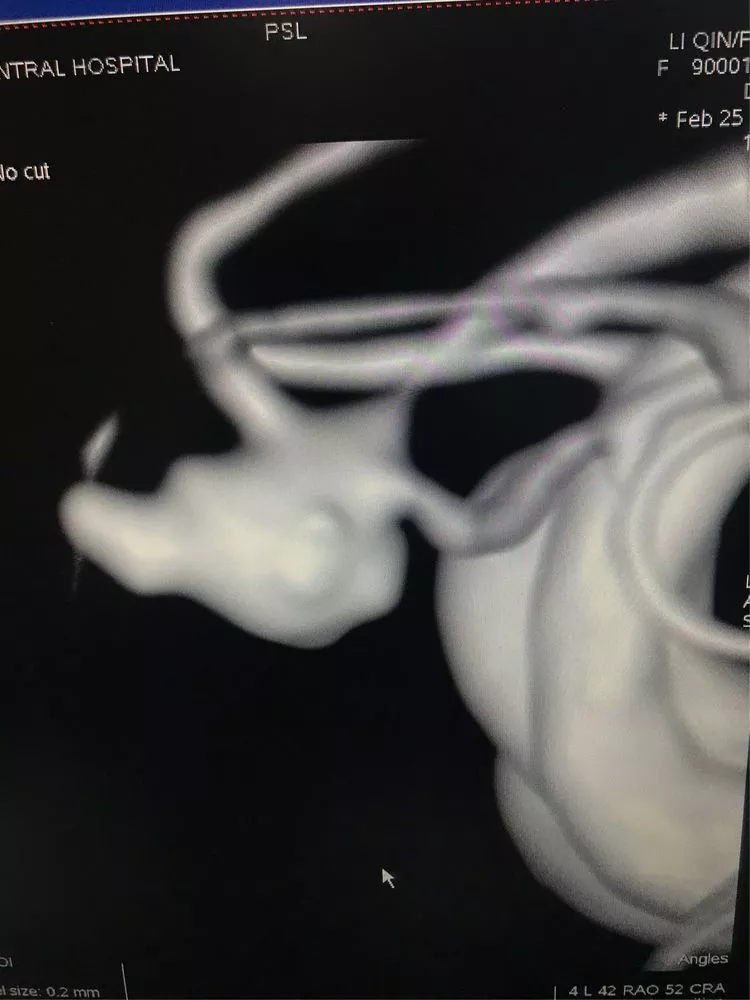

1、动脉瘤形态不规则,有二个大的子瘤。

3、宽颈,同时对侧A1缺如,前交通动脉必须保持通畅。

换了一个角度进行填塞,主要是观察前交通的部位,避免弹簧圈影响到前交通。第一个成篮圈最为关键,既要避免分隔,又要保证不影响前交通。

最后的影像。(瘤颈与前交通的切线位,没有弹簧圈突入前交通。)